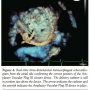

diastolic diameter, 64 mm), and impairment of left ventricular function (ejection fraction, 45%). Transesophageal echocardiography (TEE) revealed recurrent severe paravalvular leakage due to a dehiscence around the medial aspect of the sewing ring. Invasive pressure measurements revealed secondary pulmonary hypertension with a mean pulmonary artery pressure of 45 mm Hg. Repeat open-heart surgery was considered to require complete replacement of the mechanical valve with substantial risks even in this young patient. Real-time three-dimensional (3D) TEE (iE 33 [Philips Medical Systems] with an X7-2t TEE probe) allowed exact location of the leakage and sizing, indicating a defect size of 5.4 x 11 mm (Figures 1 and 2). The vena contracta area defined by 3D color Doppler was found to be 0.47 cm2. Thus, interventional closure of the

Discussion. The ability of 3D TEE with off-line analysis to generate en face views of the mitral valve dehiscence allowed a simplified interrogation of defect dimensions in our patient. Surprises with regard to the device size or the ability to anchor the device in a stable position were reduced. The dimensions of the defect were analysed using two modalities of 3D TEE: (1) zoom mode; and (2) full-volume wide-angle acquisition with color Doppler allowing analysis of the vena contracta of the defect

(Figures 1 and 2). Analysis was done off-line with commercially available software (3DQ, QLAB-Version 7.0, Philips Medical Systems).